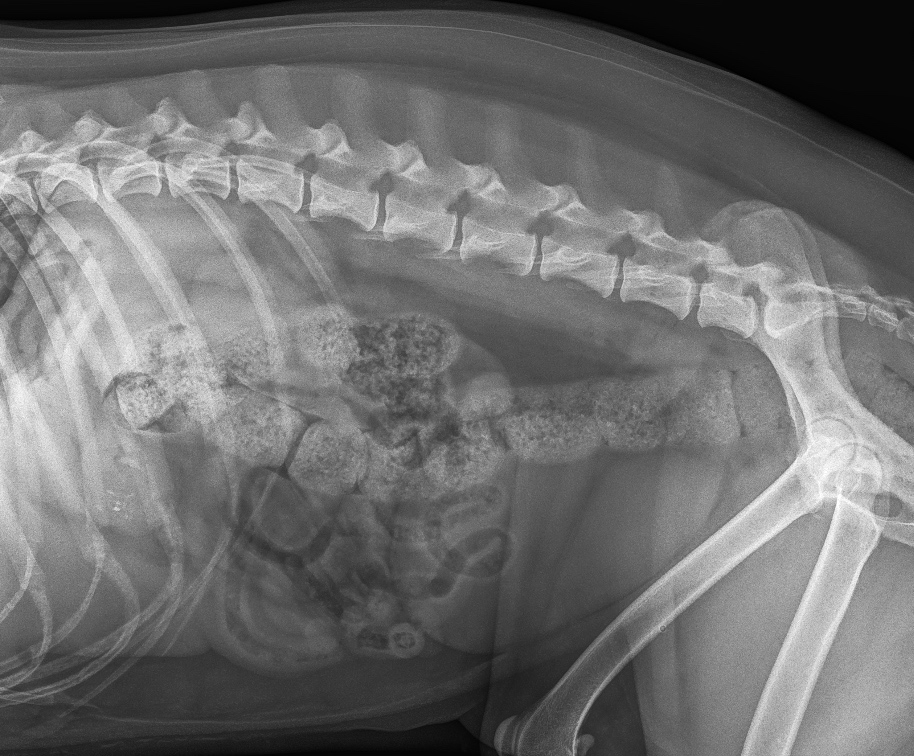

The Whyalla Veterinary Clinic has a new Shimadzu MUX10 Xray machine for high quality radiographs and a new Agfa XD14 Csi Tethered panel to produce outstanding direct digital Xrays from the images from the Shimadzu MUX10 Xray machine.

The XD14 CsI Tethered Panel is an integral part of an Agfa HealthCare’s Instant DR solution, which includes the NX image acquisition software with MUSICA3 processing and detector. These cassette-less and filmless solutions provide a range of workflow benefits that improve quality, productivity and speed up exam time.